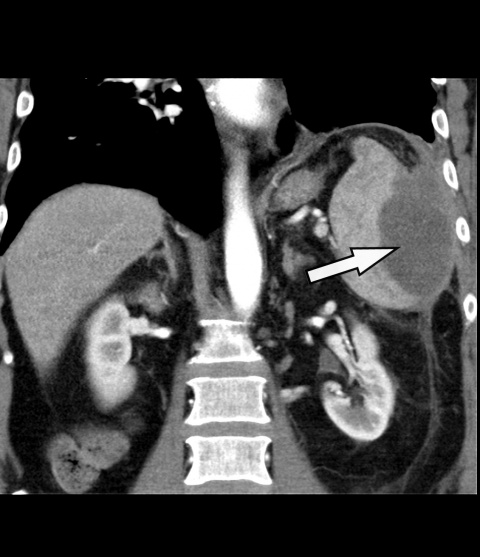

Als weiterführende Diagnostik erfolgte unmittelbar im Anschluss eine kontrastmittelverstärkte CT des Abdomens -[Philips® -Ingenuity 64 x 0,625 mm, SD 5 mm, KI 5 mm, Pitch: 1,142; KM Dosis 100 ml/Ultravist300®, Flussrate 3 ml/sec]. In der Milz zeigte sich eine 9 x 8 x 6 cm große, zentral hypodense (25 HE¹) Raumforderung mit randständig teils inhomogener überwiegend linearer Kotrastmittelaufnahme, eine Imbibierung des umliegenden Fettgewebes und eine Verdickung des Retroperitoneums – insgesamt passend zu einem Abszess (Abbildung 1). Auf genaueres Befragen gab der Patient an, 3 Monate zuvor beim Sturz auf einen Baumstamm ein links-abdominelles Anpralltrauma erlitten zu haben. So folgerten wir, dass es im Rahmen dieses Traumas zu einem Milzhämatom und im weiteren Verlauf zu dessen Superinfektion mit Abszedierung gekommen war.